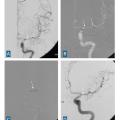

L’imagerie cérébrale intervient également dans le suivi et la prise en charge des complications tardives. En cas de vasospasme résistant au traitement ­médical optimal, une procédure endo­vasculaire est menée, incluant une dilatation chimique et éventuellement mécanique (fig. 5).